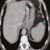

Екстрена гастректомія з пластикою голодною кишкою під час операції Льюїса через ішемію культі шлунка: опис клінічного випадку

Автори: Лукашенко А.В. Кулай А.А. Нагорний А.В. Віноградова М.О. Т. 15, №4 (60)